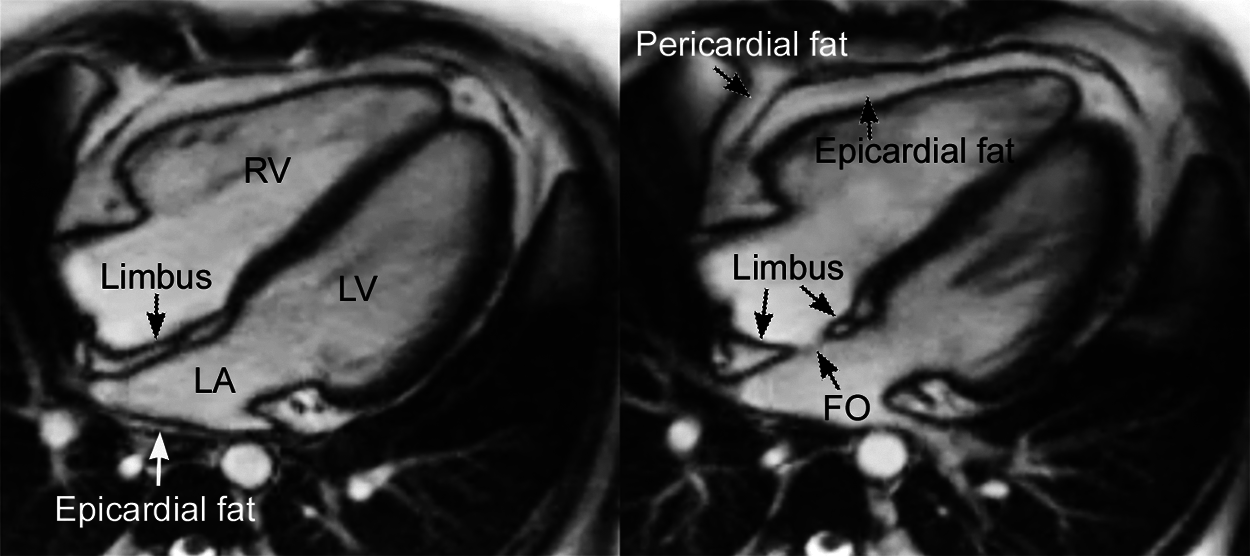

Figure 2: Cine magnetic resonance images of the normal heart in 4-chamber planes from an obese teenage female showing the two components of the interatrial party wall, the thin membranous fossa ovalis (FO) and the thick surrounding limbus. The limbus consists of the two thin muscle layers (shown as dark strips) and an interposing layer of fatty tissue (bright central zone). Both muscle and fatty tissue layers appear to be the infolding atrial wall and the epicardial fat, respectively. Normally, the central fatty layer is thin and can be hardly identifiable. LA, left atrium; LV, left ventricle; RV, right ventricle